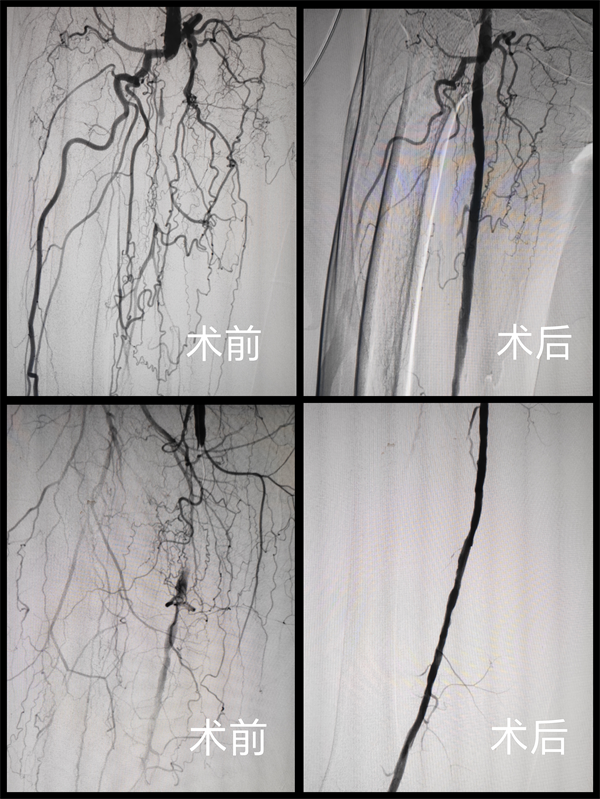

此次两名成功治疗的患者,一位是患有短段股动脉重度钙化闭塞合并尿毒症及糖尿病的老年患者,另一位则是患有股动脉长段硬化闭塞的患者。介入血管外科团队术前进行了细致的多模态影像学评估,术中凭借精湛的操作技术,精准运用Jetstream系统成功开通了闭塞段血管,术后造影显示管腔获得满意,血流恢复通畅。两位患者术后次日即可下床活动,术前的腿部冷痛、麻木症状消失,治疗效果显著。